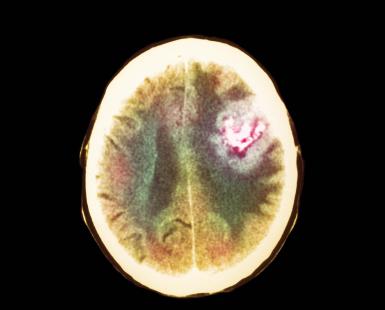

Trois patients atteints d’un glioblastome de mauvais pronostic ont pu bénéficier d’une nouvelle approche visant à protéger la moelle osseuse (MO) des effets toxiques de la chimiothérapie, à savoir une greffe de leurs propres cellules souches hématopoïétiques modifiées ex vivo.

Le gène MGMT est activé dans de nombreuses tumeurs cérébrales de grade IV, ce qui réduit l’effet cytotoxique antitumoral des agents alkylants car les lésions d’ADN induites par les agents alkylants sont réparées.

De 50 à 60 % des patients atteints de glioblastome ont une tumeur qui héberge le gène MGMT activé et qui résiste donc à la chimiothérapie. Une approche consiste à administrer de la benzylguanine (qui inhibe le gène MGMT) en combinaison avec l’agent alkylant. Mais cette association est beaucoup trop toxique pour les cellules de la MO, aboutissant à une réduction des doses ou à l’arrêt de la chimiothérapie.